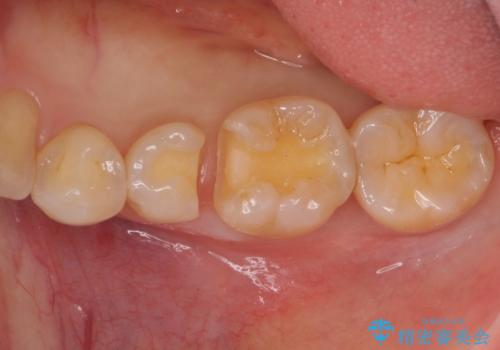

- 14万円(左下5・左下6 emaxプレスインレー 7万円 x 2)費用は治療当時の料金となります

向かい合う銀歯を同時にやり変えることで、コンタクト(歯と歯の間の形)を理想的に仕上げることができ、ものも挟まりにくいように仕上げることができます。